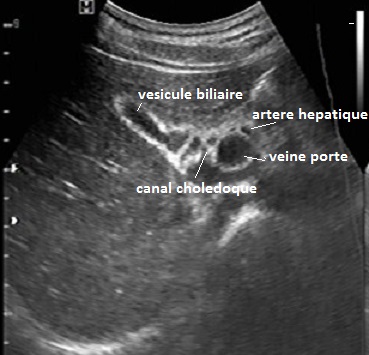

- Coupe hypochondre droit incline oblique

superieure droit( transverse recurrent "Tete de

Mickey ") a travers le foie droit et le tronc

de la vein porte . Artere hepatique , le canal choledoque et la

vesicule biliaire peut en vue totalement sủr cette

coupe |

Les voies biliaires intrahepatiques ne sont habituellement

voie biliaire principale est inférieure a 6 mm. La vesicule biliaire est en forme ovoide a

les coupe hypochondre droit et coupe intercostale . Le canal choledoque normalement a diametre <

6mm et + de 1mm de > 60 age. et en vue sur coupe

hypochondre droit incline oblique superieure droit (

en forme de " Tete de Mickey " ) et coupe intercostale sur

la ligne axilaire anterieur droit . Canal cystique est

tres difficile de voyait

Image echographique normale

du foie droit en coupe intercostale de

la ligne axilaire anterieuse droit ( long sagitale -

vesiculaire ) . On en

voyait foie droit , branche droit de la veine porte

, vesicule biliaire et artere hepatique |

Coupe

transverse recurrent bifurcation portal et vesicule

biliaire . Le foie droit ,la vesicule biliaire , la

bifurcation de la veine porte et canal choledoque ,

artere hepatique peut en voyait sur cette coupe |